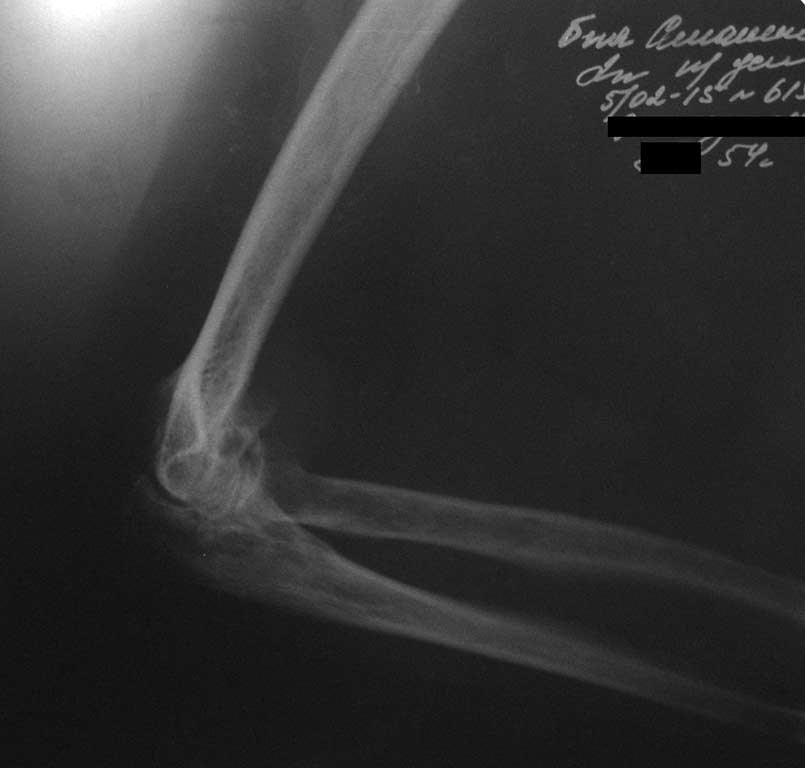

У женщины 54 лет имеются последствия закрытого вывиха костей предплечья...

Травма 08.11.14 г., окончательное вправление лишь 10.11.14 г., тогда же появились признаки нейропатии локтевого нерва, они остаются до сих пор.Движения в суставе качательные, практически анкилоз в положении 90 град.

Снимки КТ в приложении.